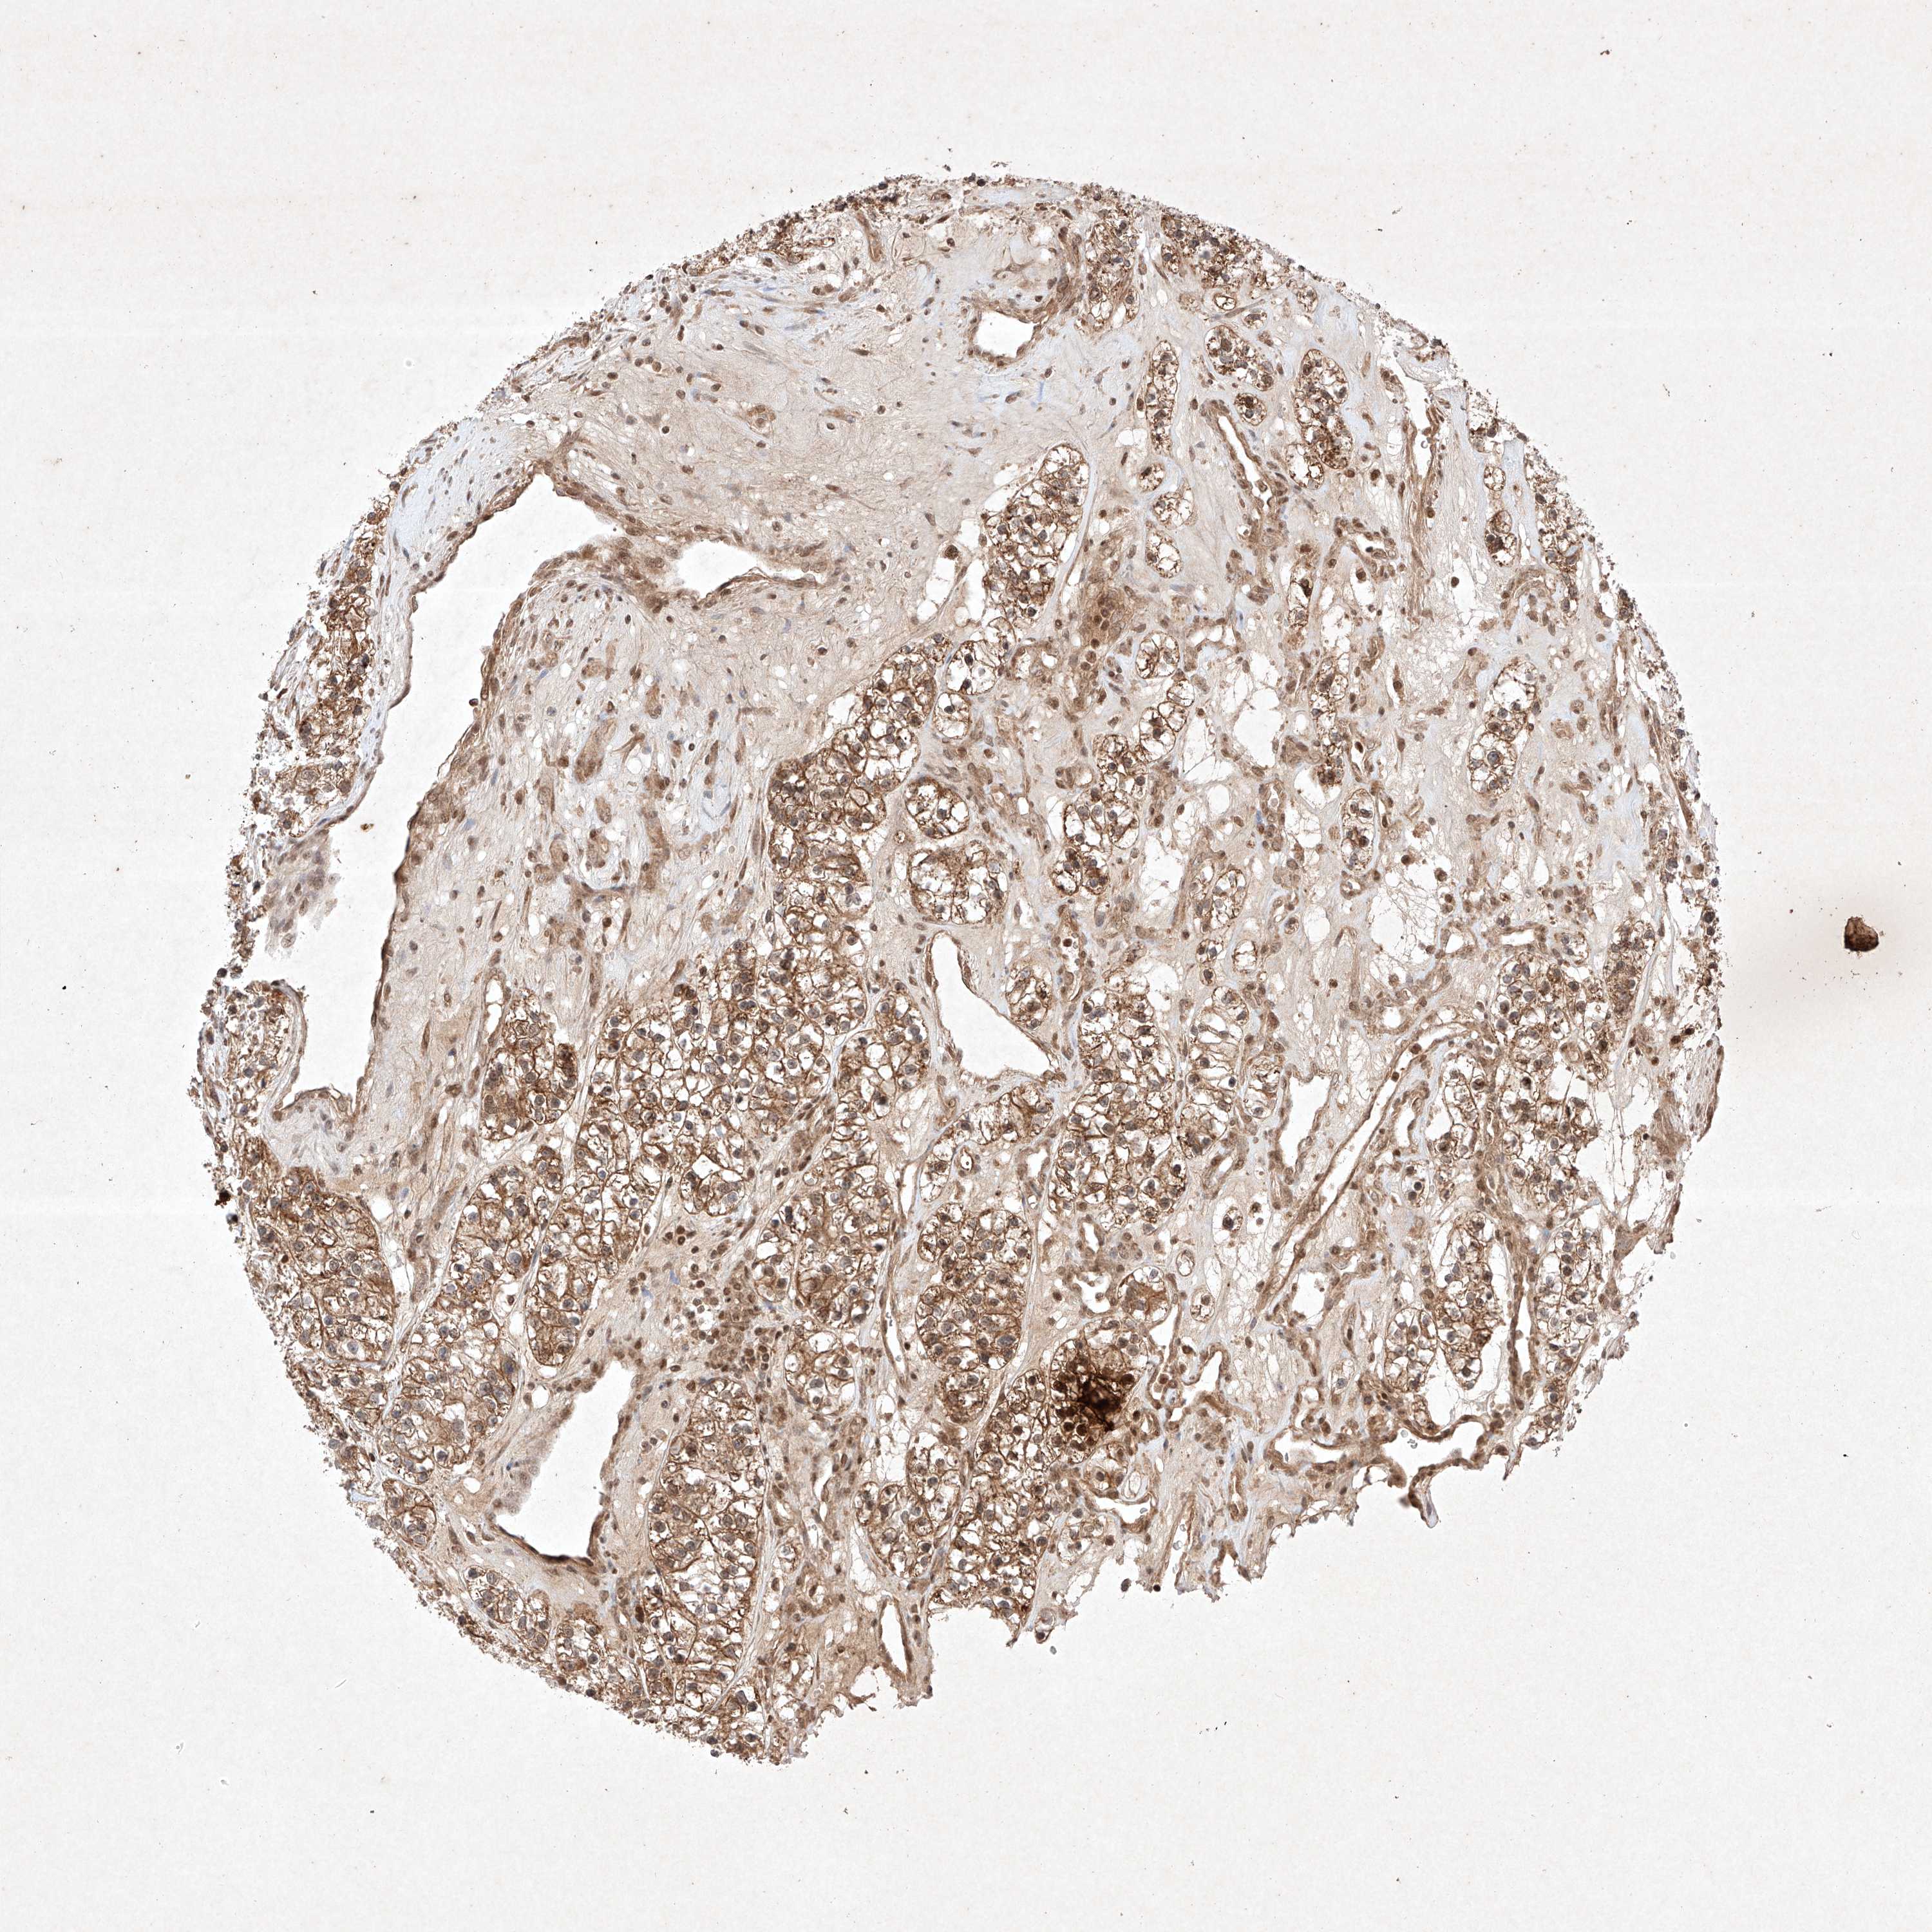

TCGA RNA samplesi

RNA-seq data is reported as average FPKM (number Fragments Per Kilobase of exon per Million reads), generated by the The Cancer Genome Atlas (TCGA) .

Normal distribution across the dataset is visualized with box plots, shown as median and 25th and 75th percentiles. Points are displayed as outliers if they are above or below 1.5 times the interquartile range. FPKM values of the individual samples are presented next to the box plot.

Average pTPM 7.3

Number of samples 521